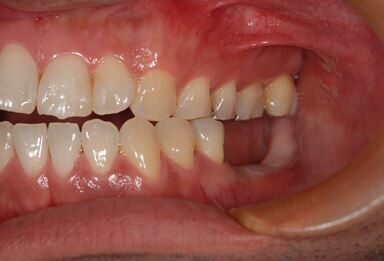

| 性別/年齢 | 男性 / 32歳 | ||||||||||||||||||||||||||||||||

| 主訴 | 銀歯がはずれたところの治療と、インプラント治療相談。 | ||||||||||||||||||||||||||||||||

| 治療方針 | 欠損部分をインプラント治療により、機能的・審美的回復を行う。 | ||||||||||||||||||||||||||||||||

| 治療内容 | インプラント2本、ハイブリッドセラミッククラウン2本 | ||||||||||||||||||||||||||||||||

| 総治療費 | 399,000円 | ||||||||||||||||||||||||||||||||

| 治療期間 | 7ヶ月 |